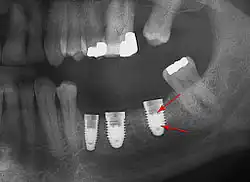

Зубной (дентальный) имплантат (англ. implant «имплант») — искусственно изготовленная, чаще всего многокомпонентная конструкция, используемая для внедрения в костную ткань челюсти с последующим сращением (остеоинтеграцией) с целью протезирования. Имплантаты замещают собой корни утраченных зубов, позволяя впоследствии провести восстановление зубного ряда.

Внутрикостные имплантаты по форме разделяют на корневидные, пластиночные и комбинированные. Наибольшее распространение имеют корневидные имплантаты, которые могут быть цилиндрической или конической формы.